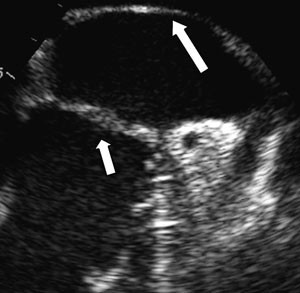

Transtorakal ekkokardiografi var ikke tilstrekkelig til å stille en sikker diagnose. Vi valgte derfor å gå videre med transøsofageal ekkokardiografi, som viste at membranen dekket en relativt stor del av atriet (fig 3). Det så ut til å være god passasje for blodstrømmen, siden det ikke var tegn til utvidelse av atriet proksimalt for membranen. Det var heller ikke andre tegn til obstruksjon, som tåkevirvler i den bakre del av atriet eller retrograd blodstrøm i lungevenene. Membranen var lokalisert basalt for aurikkelen. Det dreide seg dermed om en venstre atrie-membran.

Den transøsofageale undersøkelsen har betydelige fordeler fremfor den transtorakale når det gjelder strukturer i atriene, pga. av fysiske begrensninger ved ultralydteknologien. Hos denne pasienten kunne transøsofageal ekkokardiografi bekrefte diagnosen og belyse betydningen av membranen for blodstrømmen.